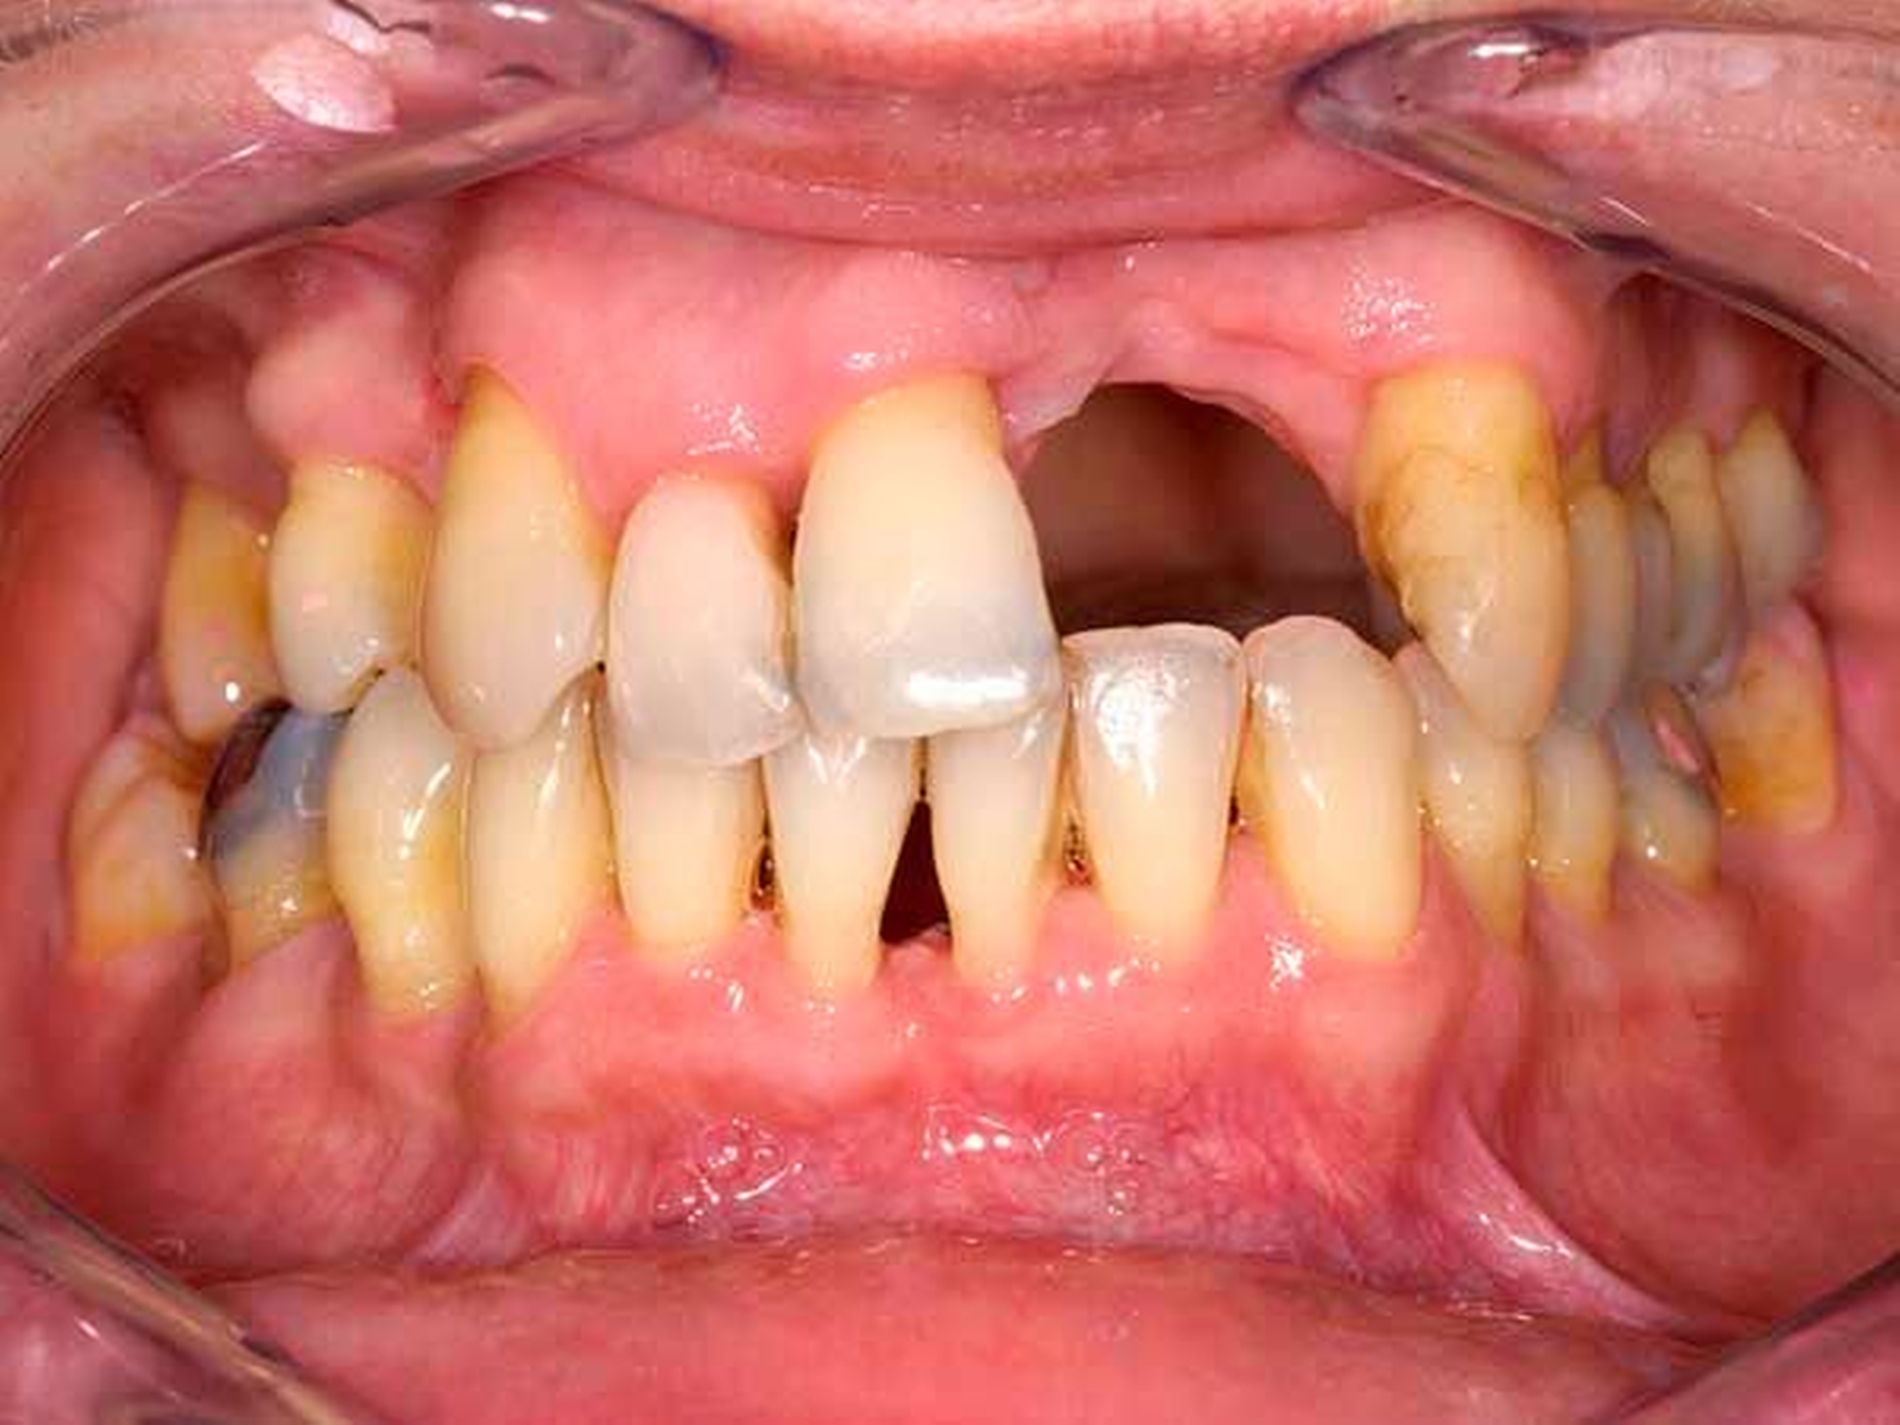

Das Orthopantomogramm (Abbildung 7) zeigt die Gebisssituation eines 89-jährigen Patienten mit kardiovaskulärer Anamnese (Herzinfarkt, Stent-Implantate) und deutlich reduziertem, fast hinfälligem Allgemeinzustand. Der Patient erhält 14(!) verschiedene Medikationen. Der überweisenden Kollegin erschien die Behandlung in der Praxis zu riskant. Nach Abschluss der Extraktionstherapie stellte sich der Patient zur prothetischen Beratung und Weiterversorgung an unserer Poliklinik vor. Im Oberkiefer wurde ein totaler Zahnersatz geplant. Im Unterkiefer verblieb ein karies- und füllungsfreies Restgebiss von 33 nach 42 (Abbildung 8). Aus gesundheitlichen Gründen schied eine Präparation der karies- und füllungsfreien Zähne für die Aufnahme von Doppelkronen oder metallkeramischen Kronen mit oralen Fräsungen aus.

Front- und Eckzähne sind aufgrund ihrer Anatomie grundsätzlich schlecht für die Aufnahme von Gussklammern geeignet. Die Lösung in diesem zweiten Fall bestand in der Anwendung zweier geteilter Klammern (Roach-Klammer), ausgeführt als Druckanker (Abbildungen 9 und 10). Lingual wurden die Zähne 33 und 42 mit den oralen Klammerarmen großflächig von disto- nach mesioapproximal gefasst. Gegebenenfalls müssen, nach Augenmaß senkrecht zur Einschubrichtung, die Tuberculi und der distoapproximale Kontaktpunkt im Schmelz mit einem Diamantfinierer leicht abgeflacht werden. Die Präparation für die orale Klammerauflage in Höhe der Tuberculi muss konsequent als Stufe von 1 mm Tiefe parallel zur Okklusionsebene eingeschliffen werden. Die Auflage selbst ist in den oralen Klammerarm integriert. Die vestibulären Retentionsarme liegen dem Zahn nicht passiv an, sondern stehen unter Vorspannung und drücken den Ankerzahn bei eingegliedertem Zahnersatz aktiv gegen das starre Widerlager der oralen Umfassung. Dies sichert in Verbindung mit der weiten, fast geschiebeartigen oralen Fassung und der integrierten Klammerauflage eine akzeptable Kippmeiderfunktion.

Die großflächigen Umfassungen der oralen Ankerzahnflächen erhöhen das Kariesrisiko, dem kann mit adäquater Mundhygiene und Fluoridierung begegnet werden. Zur Optimierung der parodontalen Hygienefähigkeit wurden die Regeln der „Grenzraumgestaltung nach Marxkors“ (brückenzwischengliedartige Gestaltung des ersten Prothesenzahnes mit metallischer Basis, Durchspülbarkeit, Insertion des sublingualen Bügels in den Sattel eine Prämolarenbreite hinter dem endständigen Zahn [Marxkors, 2007]) konsequent umgesetzt (Abbildungen 11 und 12).

Alternative prothetische Therapieoptionen für diesen Fall wären sicherlich kombiniert festsitzend-herausnehmbarer Zahnersatz in der Ausführung als Kronen und Modellguss oder eine Doppelkronenverankerung. Diese schieden aufgrund der geringen körperlichen Belastungskapazität aus, sowohl im Hinblick auf die Anzahl der notwendigen Zahnarztbesuche als auch auf die physischen Belastungen während der prothetischen Behandlung. Gerade bei notwendigen Verankerungen im Front- und Eckzahnbereich sollten die Grundregeln der Prothesendynamik konsequent beachtet werden: eine funktionelle Extension des freiendenden Sattels, Beschränkung der Zahnreihe auf die ersten zwei Drittel der Sattellänge, um die Hebelkräfte gering zu halten. So wurde in diesem Fall auf eine Aufstellung der zweiten Molaren verzichtet.